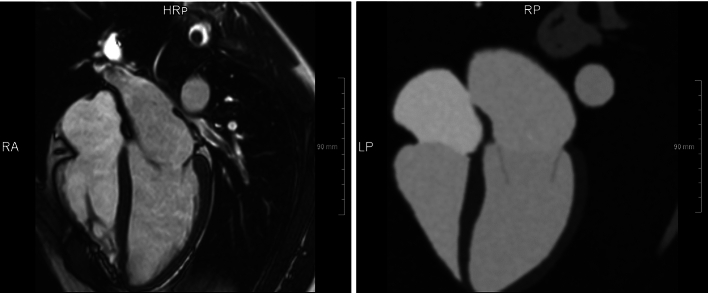

We compared the simulated image data to volunteer data acquired with similar parameter settings as suggested for rLAX18 (Table 3).

Figure 6 shows corresponding slice orientations. It can be observed that intensity distributions appear similar. However, typical artifacts from hemodynamics as well as small structures not included in our anatomical model are missing in the simulated data, and anatomical regions appear more homogenous.

Fig. 6.

Real vs synthetic images comparison. MRI acquired on healthy volunteer (left) with similar parameters to our rLAX18 generated synthetic image based on the anatomy derived from CT and intensities from CMR (right)